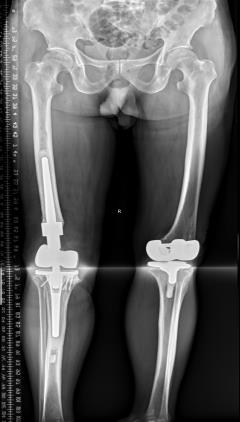

该科擅长对膝关节严重创伤(包括股骨远端骨折、髌骨骨折、胫骨平台骨折等)、膝骨关节炎阶梯化治疗、保膝治疗、膝关节微创单髁置换术、全膝关节置换术、膝关节翻修术具有丰富的临床诊疗经验,追求微创、无痛、快速康复。

对膝关节骨性关节炎采取阶梯化治疗方案,坚持中西并重、内外兼治的原则,取得满意的治疗效果。早期利用中医中药的传统优势,使用中医外治法,例如烫熨治疗、中药涂擦、雷火灸、中药塌渍等,同时辩证内服本院中药制剂及内服方药以及配合西药治疗,开展健康教育,运用运动疗法、物理治疗等辅助支持;中期开展软骨修复、截骨术、单髁置换术、髌股关节置换术等;对于终末期的膝关节OA采用全膝关节置换术。